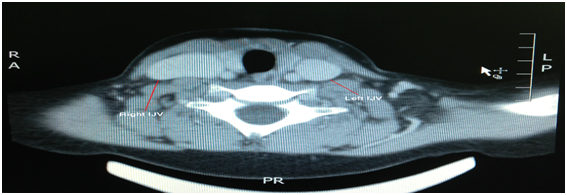

A ten year old male with no particular past medical or surgical history presented with history of right neck intermittent swelling since long time. This swelling became more prominent the past 4years. Parents noticed this swelling since early childhood, which was according to them increasing in size during coughing, straining, and any other Valsalva like manoeuvre. This swelling was occasionally associated with non-alarming shortness of breath while sleeping, especially when the child has an upper respiratory tract infection. He has been frequently seen in different hospitals for the same, and the parents were worried because of no definite diagnosis was made. On physical examination, he was generally healthy boy, with no dysmorphic features. Neck examination at rest showed no abnormality, however; on performing valsalva manoeuvre the swelling started to appear in the right side of the neck anterior triangle and posterior to the SCM muscle (Figure 1). On palpation there was fullness in the right side anterior triangle of the neck which was pushing the SCM slightly anteriorly. The mass was about 4x5cm, smooth surface with well-defined anterior surface, not warm, not tender, and not pulsatile. The mass completely disappeared when the child is relaxed. On the other side of the neck there was no swelling appreciated (Figure 2). Computed tomography revealed dilatation of right internal jugular vein, more toward the inferior part of the vein. There was no mass causing compression or obstructing the drainage of the vein (Figure 3).

Figure 3 Contrast Enhanced CT scans of the neck: Right Internal Jugular Vein Phlebectasia.